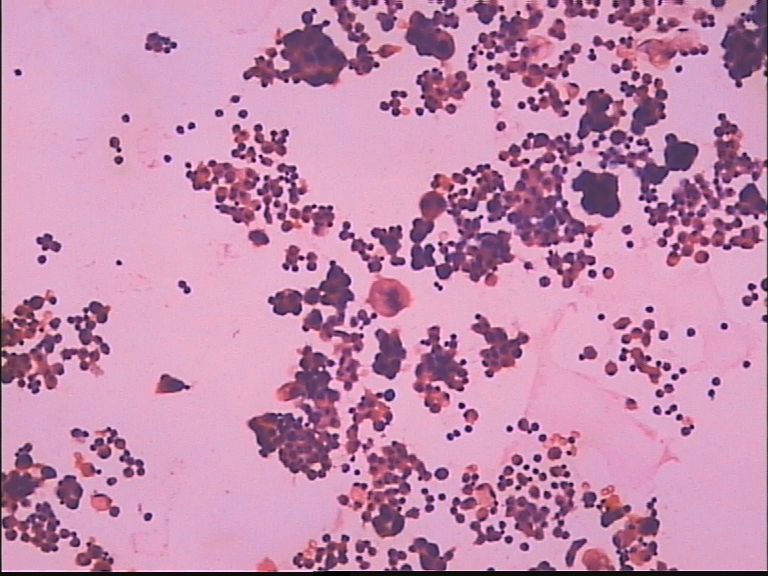

胸水 男67岁

• 胸水 男67岁图2

图2